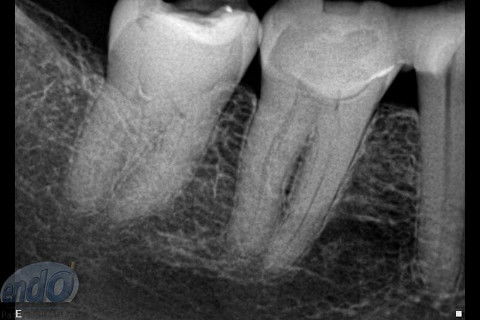

Tratamento Endodôntico dos Dentes 45 - 46 - 47

Seguem 3 casos clínicos realizados esta semana em uma cliente que está passando por um tratamento estético. O dente 47 apresentava calcificação da entradas dos canais radiculares, provavelmente, devido a uma pulpotomia realizada no passado. Desta forma, foi dedicada uma consulta de aproximadamente 2 horas para a realização deste procedimento. Os dente 45 e 46, por apresentarem canais radiculares com menor complexidade, foram tratados, simultaneamente, em sessão única com duração de aproximadamente 2 horas e 15 minutos.

Os três dentes foram tratados seguindo a técnica da FOP-UNICAMP, na qual é realizada patência e ampliação do forame apical. A instrumentação foi realizada com instrumentos rotatórios e como substância química auxiliar foram utilizados o ENDOGEL e o EDTA 17%. A irrigação ativa foi realizada com soro fisiológico. Os canais foram obturados com guta-percha e cimento PulpCanal Sealer, pela técnica de ondas contínuas de condensação.

Os procedimentos pré-restauradores nos dentes 46 e 47 envolveram apenas a confecção de núcleo de preenchimento em resina composta (Z250 B0,5). No dente 45 foi instalado um pino de fibra de vidro (FGM) e confeccionado núcleo de preenchimento em resina composta (Z250 B0,5).